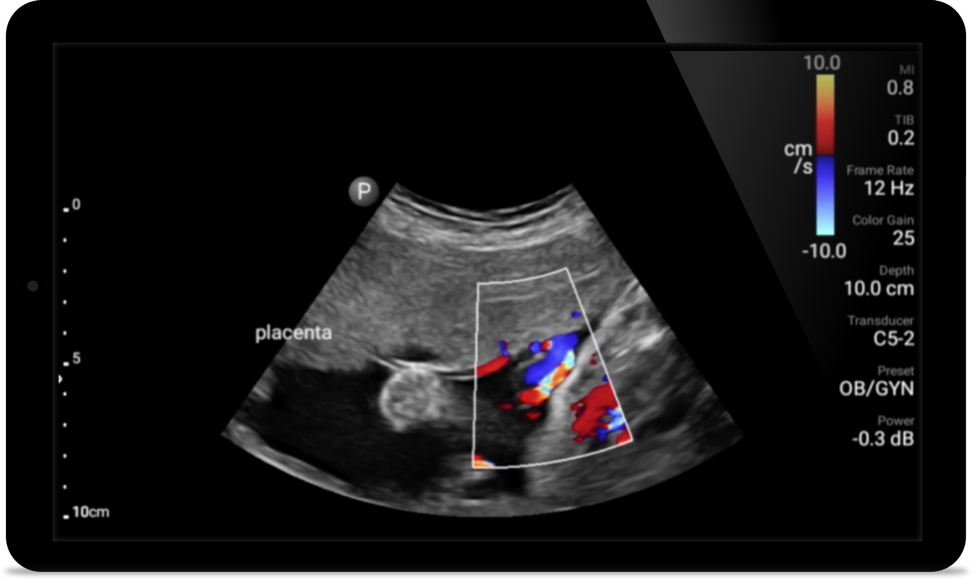

Lumify puede ayudar a obtener resultados similares a los de una tomografía computarizada de tórax al evaluar la neumonía y el síndrome de dificultad respiratoria en adultos.

• Rango extendido de frecuencias de operación entre 12 y 4 MHz • Tamaño de apertura: 34 mm • 2D, Doppler orientable a color, Modalidad M, XRES avanzado e imágenes armónicas multivariables, SonoCT • Imágenes de alta resolución para aplicaciones superficiales: tejidos blandos, vasculares, superficiales, musculoesqueléticos y pulmonares • Marcador de línea central • Transductor USB-C con cable reemplazable